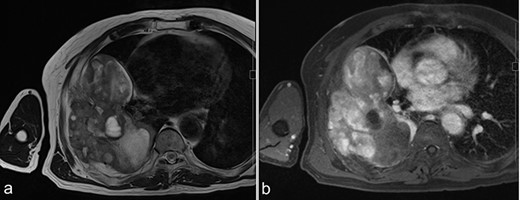

A 72-year-old man was referred to our department with a suspected tumor in the right rib. An abnormal shadow in the right chest was found during screening at 50 years of age. The patient was later followed up intermittently by a general physician (Fig. 1a and b). At 72 years of age, he was referred to our department because of a suspected malignant tumor. There were neither subjective symptoms nor abnormal physical findings. A blood test revealed an elevated level for alkaline phosphatase alone at 706 U/L. A pulmonary function test showed a percent vital capacity (%VC) of 78.8%, indicating a mild restrictive impairment. Plain radiography showed a radiopaque tumor measuring 12 × 9 × 18 cm that was connected to the seventh rib in the right thoracic cavity (Fig. 1c). When compared to previous images, the tumor had gradually grown over the preceding 22 years. Computed tomography (CT) showed an extra-osseous tumor-like lesion with calcification, cortical destruction of the right seventh rib and a similar small lesion in the right ninth rib (Fig. 2). Moreover, lesions were also detected in the ninth thoracic vertebral body. Magnetic resonance imaging (MRI) revealed a lower signal intensity inside the lesion compared to the muscle on T1-weighted images and a mixture of low and high intensity on T2-weighted images, while enhancement was observed in the lower intensity area on T2-weighted images (Fig. 3a and b). Bone scintigraphy and positron emission tomography/computed tomography (PET/CT) revealed an increased uptake in the right seventh and ninth ribs and ninth vertebral body, and the right seventh rib showed a high standard uptake value at 7.67 on PET/CT (Fig. 4a and b).

MRI before surgery. (a) T2-weighted MR image shows a mixture of lower and higher intensity areas. (b) An enhanced image shows enhancement in the lower intensity area on T2-weighted images.